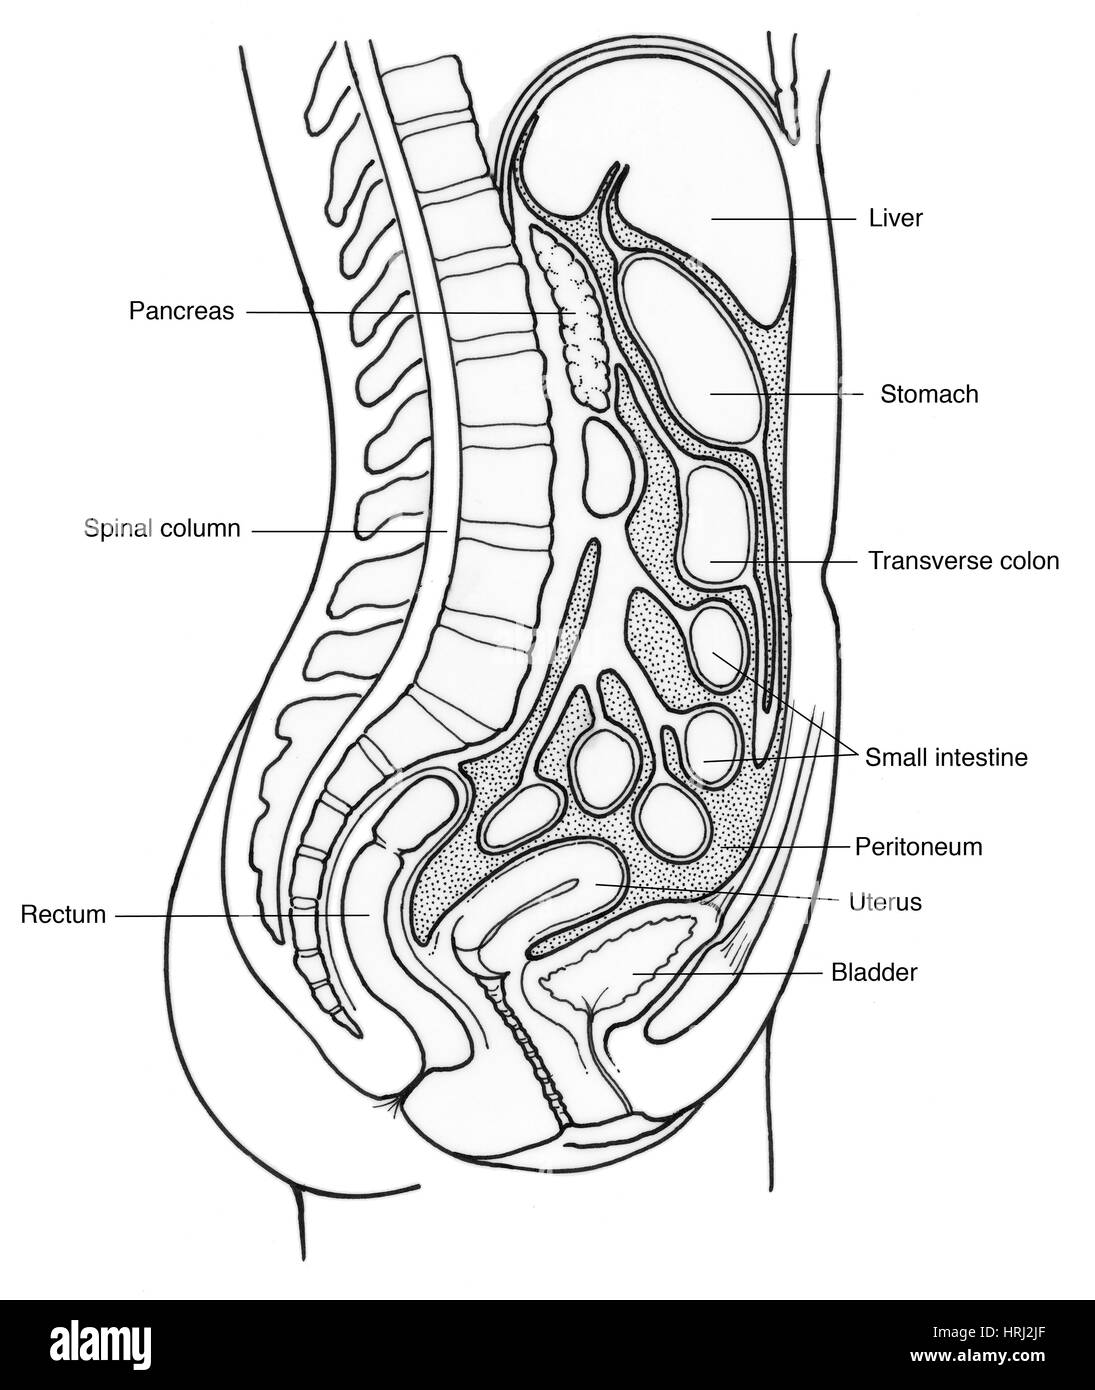

Illustration of Female Internal Organs Stock Photohttps://www.alamy.com/image-license-details/?v=1https://www.alamy.com/stock-photo-illustration-of-female-internal-organs-135006887.html

Illustration of Female Internal Organs Stock Photohttps://www.alamy.com/image-license-details/?v=1https://www.alamy.com/stock-photo-illustration-of-female-internal-organs-135006887.htmlRMHRJ2JF–Illustration of Female Internal Organs

Illustration of Female Internal Organs Stock Photohttps://www.alamy.com/image-license-details/?v=1https://www.alamy.com/stock-photo-illustration-of-female-internal-organs-135006572.html

Illustration of Female Internal Organs Stock Photohttps://www.alamy.com/image-license-details/?v=1https://www.alamy.com/stock-photo-illustration-of-female-internal-organs-135006572.htmlRMHRJ278–Illustration of Female Internal Organs